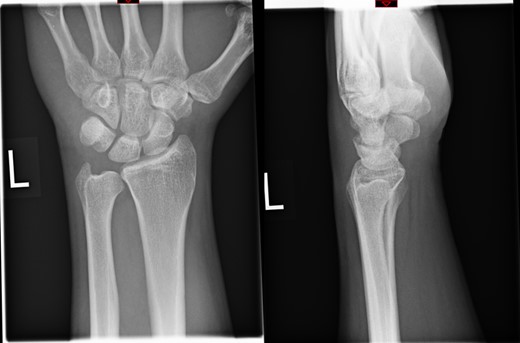

The X-rays of the patient was later reviewed by the duty radiologist and reported as a suspected dislocation of the pisiform bone, Fig. 1. Therefore the patient was recalled to the trauma clinic after three days. He was reassessed and a further three dimensional scan of the wrist was arranged. The CT scan demonstrated distal dislocation of the pisiform which appeared to lie in a ‘locked’ position beyond the distal triquetrum, Fig. 2.

The clinical diagnosis of pisiform dislocation is usually dependant on the injury mechanism and the presence of pain, swelling and tenderness over the ulnar aspect of the wrist. Our patient had pain, swelling and tenderness in the dorso-medial aspect of the wrist. The radiographs may not be able to demonstrate the dislocation of the pisiform in a standard AP and lateral views. An oblique radiograph and comparison with the contralateral side is quite often helpful. Computer tomograms are conclusive and Magnetic Resonance imaging will show the associated ligamentous and soft tissue injuries. In our patient the emergency physicians failed to diagnose the dislocation of pisiform in the initial radiographs, but CT scan confirmed the diagnosis.